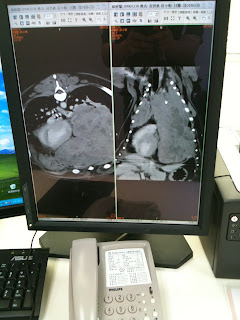

左邊那張圖是橫切面, 右邊那張圖是他仰躺的切面, 可以看得出來左胸腔原本應是空氣要為黑色的部份,都已經被腫瘤塞滿. 心臟跑到右邊, 右胸腔上半部也是腫瘤,整個胸腔只剩20%的功能

這是他看過最大最嚴重的狀況, 而小唄也是他遇過腫瘤那麼大,還能活到現在的小狗...真是奇蹟,,,而這個腫瘤也自已大到中間灰影的部份,是腫瘤本身自已中心壞死了..

這什麼狀況啊, 可惡的臭腫瘤 ....幹.